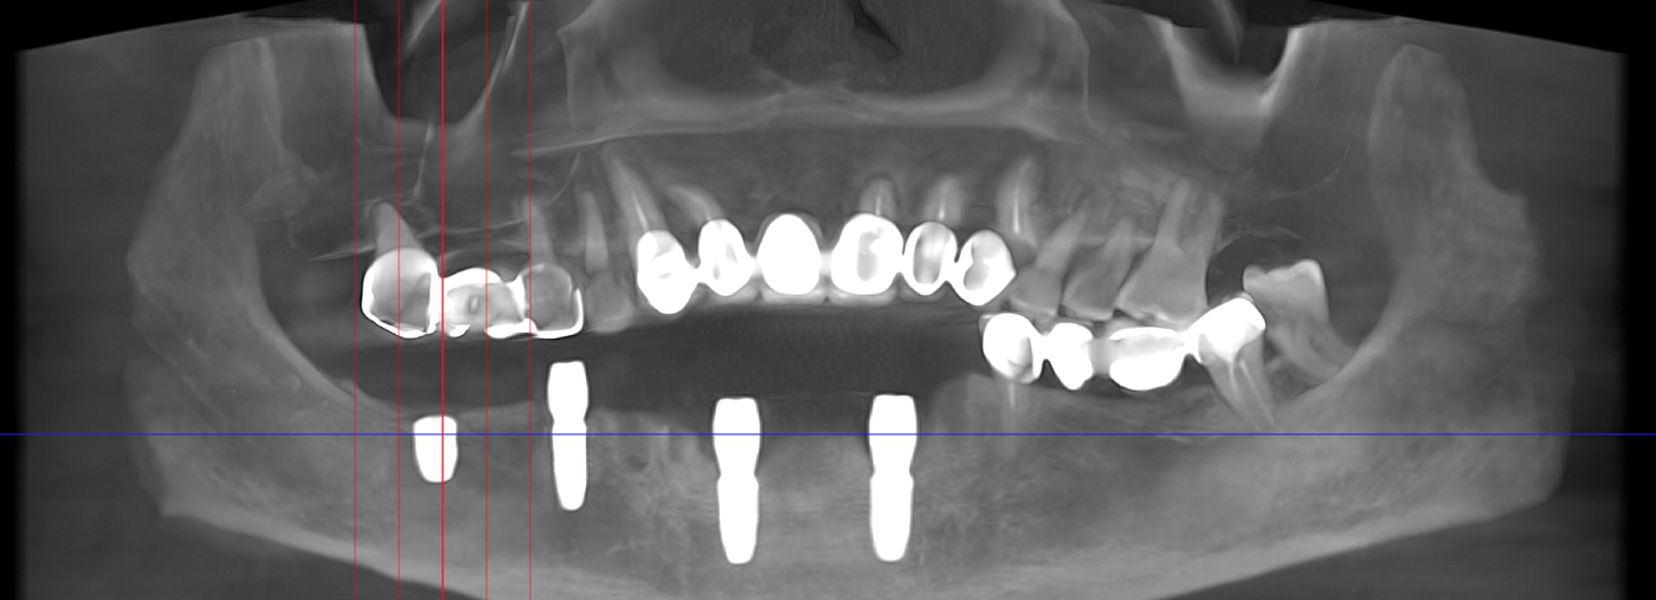

Tomografie (CBCT)

Caz 2